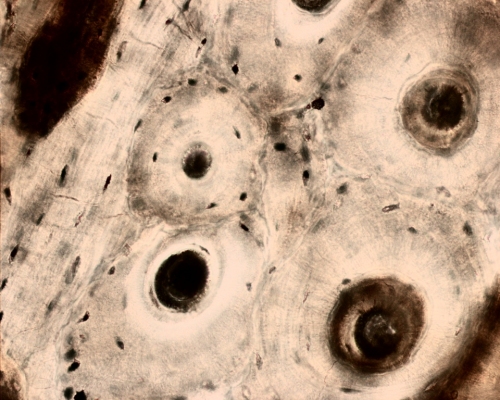

Ground section of bone